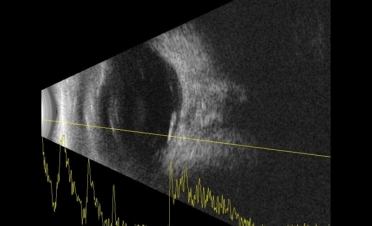

La ecografía permite observar las estructuras del globo ocular cuando la transparencia de la córnea está comprometida o cuando deseamos observar con detalle los segmentos anterior y posterior del ojo.

En ambas pruebas se observaron imágenes compatibles con un desprendimiento de retina:

Imágenes de la ecografía de Fox, un perro de raza Pomerania con desprendimiento de retina en ambos ojos. Se descartaron otro tipo de lesiones oculares. Foto: IVO. (Clicar la fotografía para ampliar)